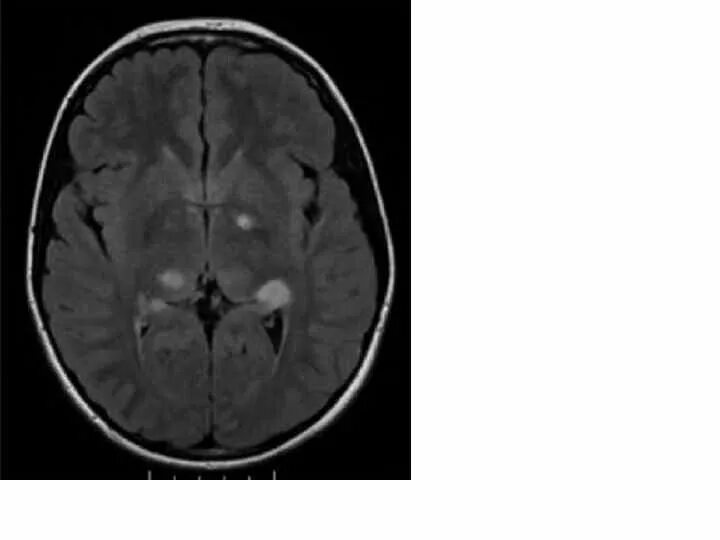

Нейрофиброматоз мрт